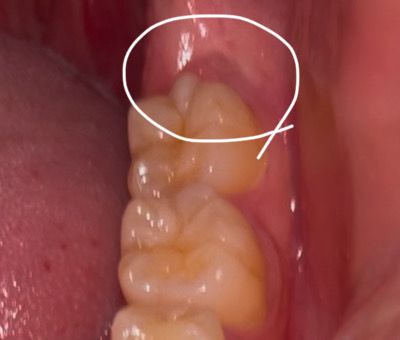

어금니 뒤 통증이 있어서 보니까 뭔가 튀어나와있어요

왼쪽 어금니 뒤에가 아파서 보니 뭔가 부어있는듯한게 있는데 단순염증인가요? 아니면 사랑니가 나오고 있는건가요? 왼쪽에 사랑니가 있다고 듣긴 했습니다.

사진에 보이는 부분은 사랑니가 매복되어 잇는 거 같습니다. 사랑니 떄문에 잇몸이 약간 튀어 나온거 같습니다.